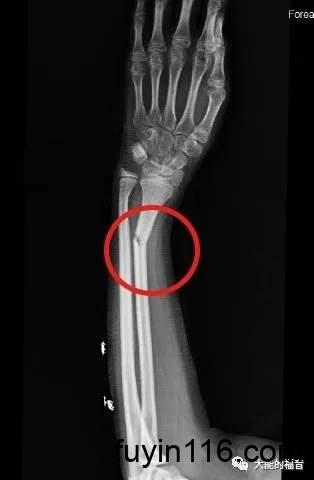

医生说,你手臂痛,头痛,而且摸着就痛,但是医生又不能把他的肉挖开了,看里面怎么样,所以医生说你去照下X光,一照X光,发现原来他里面的骨头断了。

其实,他以前骨头就断了;而X光机把他已经骨折这件事显明出来了而已。

(上图来自网络)